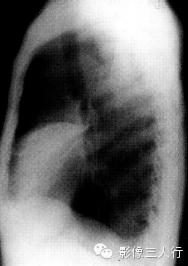

报告示范:右肺中下肺野可见大片密度增高影,上缘清晰,右心缘模糊。侧位片示病变位于右中叶。胸廓对称,气管纵隔居中。心脏大小、形态、位置正常。双侧膈肌光滑,肋膈角锐利(图1)。

图1右中叶大叶性肺炎

(B)侧位